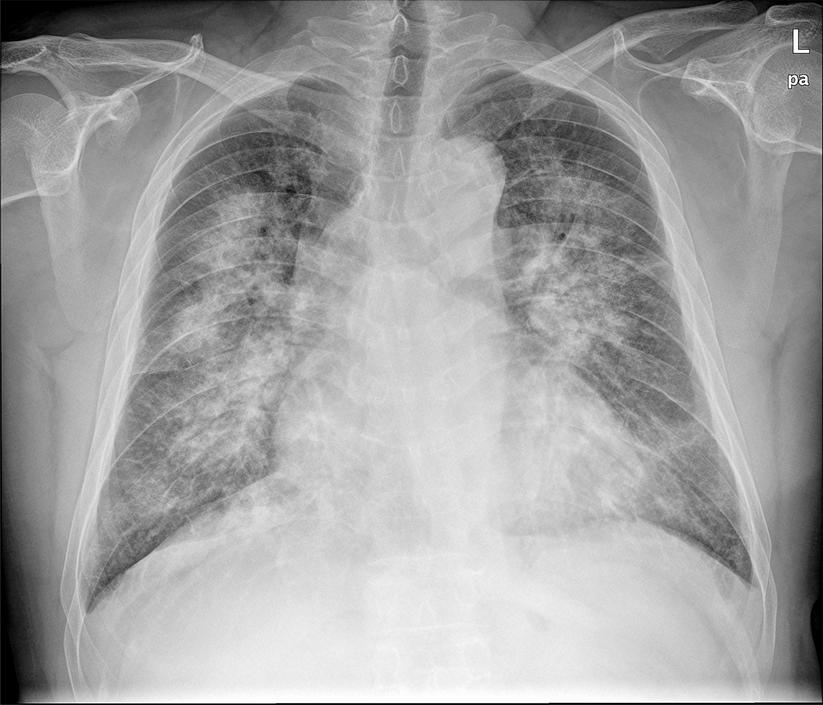

肺部病变---

强直比较常见的并发症之一就是患者的肺部会出现一些病变的情况,尤其是患者的病史比较漫长的更容易出现这样的病变,同时还会随着患者的病情的不断地加重,病变的程度也会不断地加重,所以,患者较好能够让自己的肺部得到一些好的锻炼,减轻肺部病变的症状!

强直患者的肺部病变